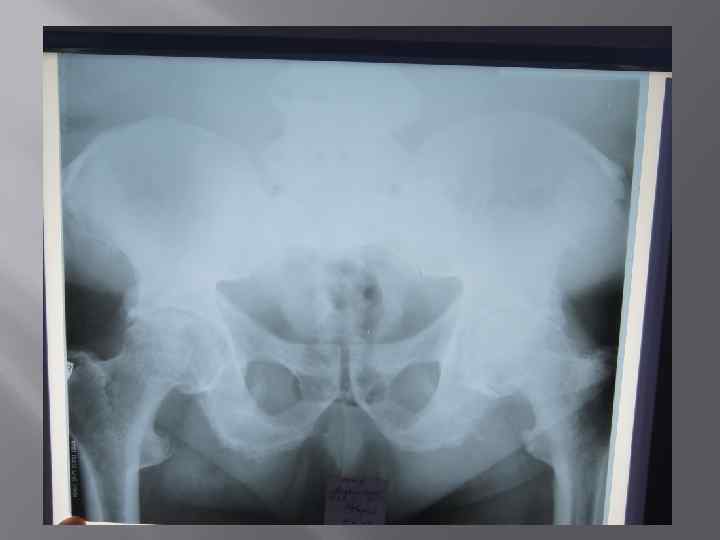

Объективно: • У пациента наблюдается дефигурация 1 плюснефаланговоговых суставов. Дефигурация левого коленного и левого локтевого суставов. Объем пассивных и активных движений в коленном суставе снижен , сгибание составляет 60 градусов, разгибание до угла 10 градусов. Объем движений в голеностопных суставах снижен и составляет 0/10 гр. Определяются тофусы в области пястно-фаланговых суставов обеих кистей, локтевых суставов, болезненность при пальпации, ограничение в объеме движений в шейном, грудном и поясничном отделах позвоночника, грудной кифоз, сглаженный поясничный лордоз, положительные симптомы сакроилеита с обеих сторон.

КЛИНИЧЕСКИЙ ДИАГНОЗ: Подагра хронического течения: рецидивирующий подагрический полиартрит (тофусы), в сочетание с анкилозирующим спондилоартритом аксиальной формы высокой степени активности, поздняя стадия, рентгенологическая стадия 4. ФК III. ХБП, 3 стадии, хронический тубоинтерстициальный нефрит с исходом в нефросклероз ( подагрическая нефропатия ), кисты почек (р СКФ CKD EPI 35 мл/мин/1. 73 м 2). Гипертоническая болезнь 2 стадия, риск 3.